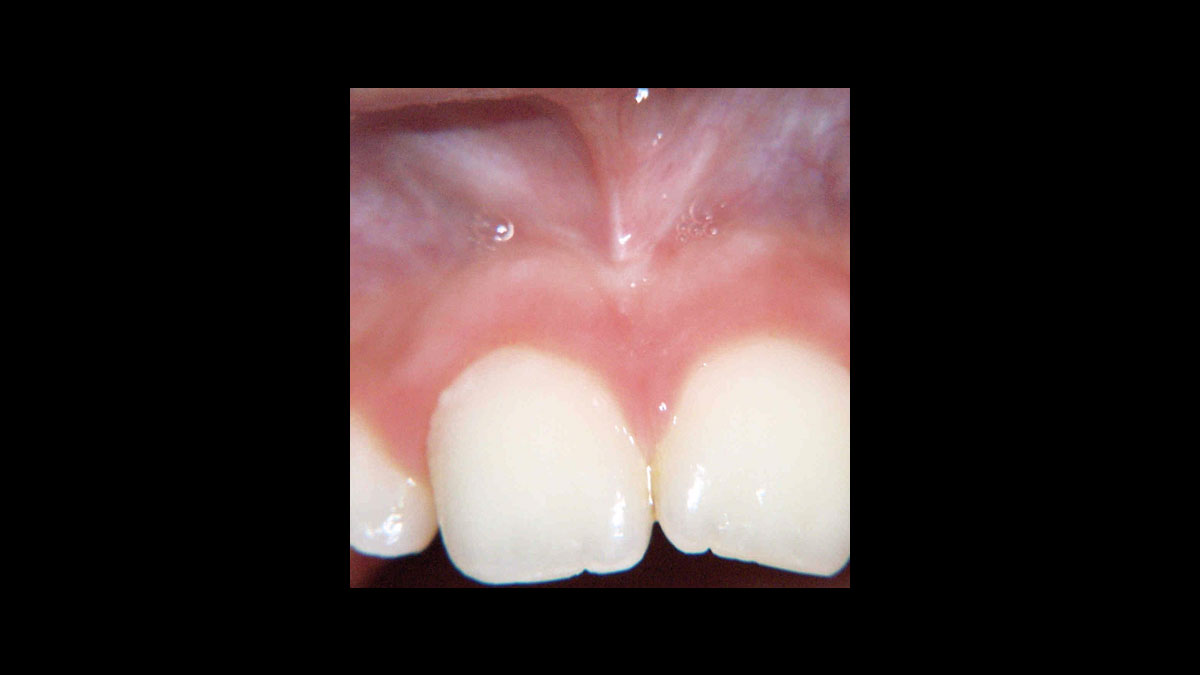

Frénectomie